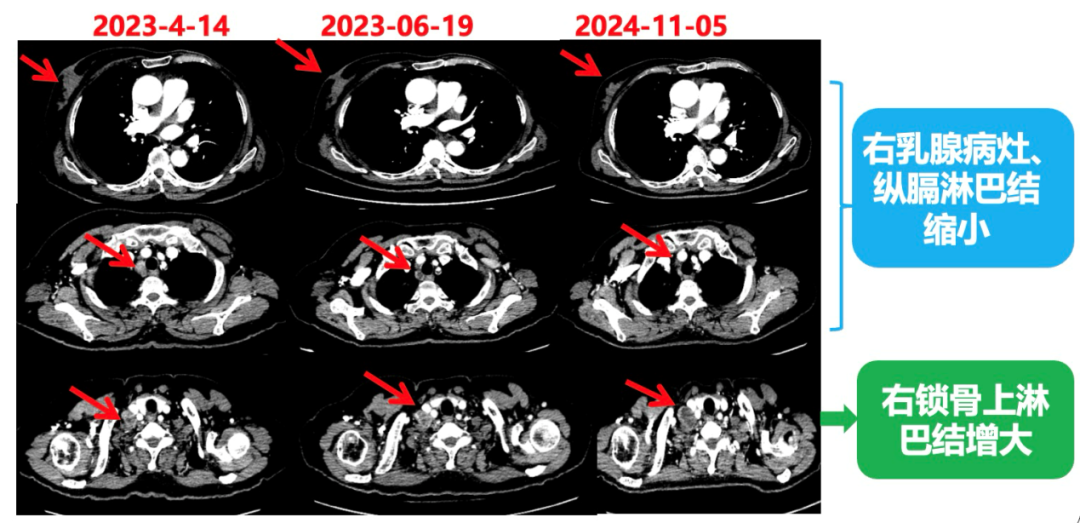

2023.6.26复查PET-CT

1.右乳外上象限乳腺癌病灶(22*16mm),对比2023-04-14 CT(26*24mm)较前缩小,FDG代谢活跃。右侧腋窝小淋巴结(5mm),较前稍缩小,代谢不活跃。右侧锁骨上区、上纵隔淋巴结转移瘤(24*18mm),现大小同前相仿,代谢活跃(SUV:6.7)。

2.现胃贲门部术后改变,术区未见明显异常活性灶。

3.左乳、左侧胶窝术后改变,未见明显异常活性灶。双肺小结节。考虑炎性结节可能,建议复查;双肺门及纵隔另反应性淋巴结。

患者已接受胃癌根治术,术后通过PET-CT对病灶情况进行了评估。目前患者采用哌柏西利联合氟维司群方案治疗,乳腺病灶已明显缩小,但锁骨上淋巴结、纵隔及肺门淋巴结未见缩小。为进一步为患者制定更精准的治疗方案,龚畅教授与曾银朵教授组织了第二次多学科联合会诊。

2024-11-5复查CT:右乳外上象限占位(11mm×9mm),较前明显缩小;上纵隔及右肺门多发淋巴结转移缩小;右锁骨上区淋巴结较前增大。余部位未见肿瘤转移及复发征象。

患者右锁骨上淋巴结较前增大,乳腺病灶明显缩小,针对是否需要进行锁骨上淋巴结及乳腺手术,龚畅教授和曾银朵教授又组织了第三次多学科会诊。